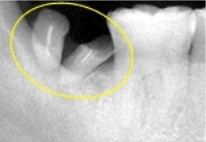

【術前レントゲン写真】

根の周りの骨が溶け、芳賀前方に傾いてきています。

まず、右下第2大臼歯を抜歯しました。